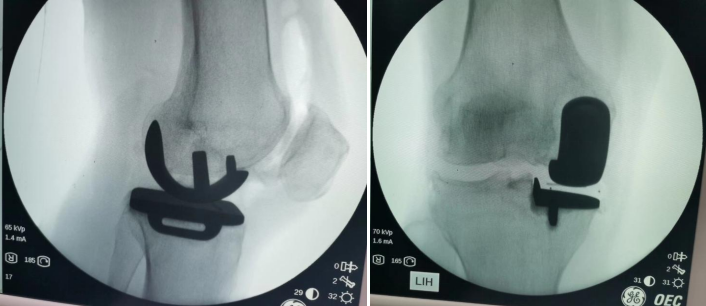

第三阶段治疗:如果患者膝关节病变集中在单侧,对侧关节里面软骨全层完整,膝关节内外侧副韧带及前后交叉韧带完好,则可行单髁置换术手术。 第四阶段治疗:膝关节内外侧关节软骨均损伤,比如类风湿性关节炎、强直性关节炎、膝关节的感染导致关节软骨破坏感染控制后等等,则需行全膝关节置换术。 (本图:左侧是截骨矫形内固定术后,右侧是全膝关节置换术后) 膝关节骨性关节炎阶梯治疗的有效路径及模式,可达到疾病有效治疗,保护有效劳动力,减少老年人因病致残生活不便引发的社会及家庭医疗负担。